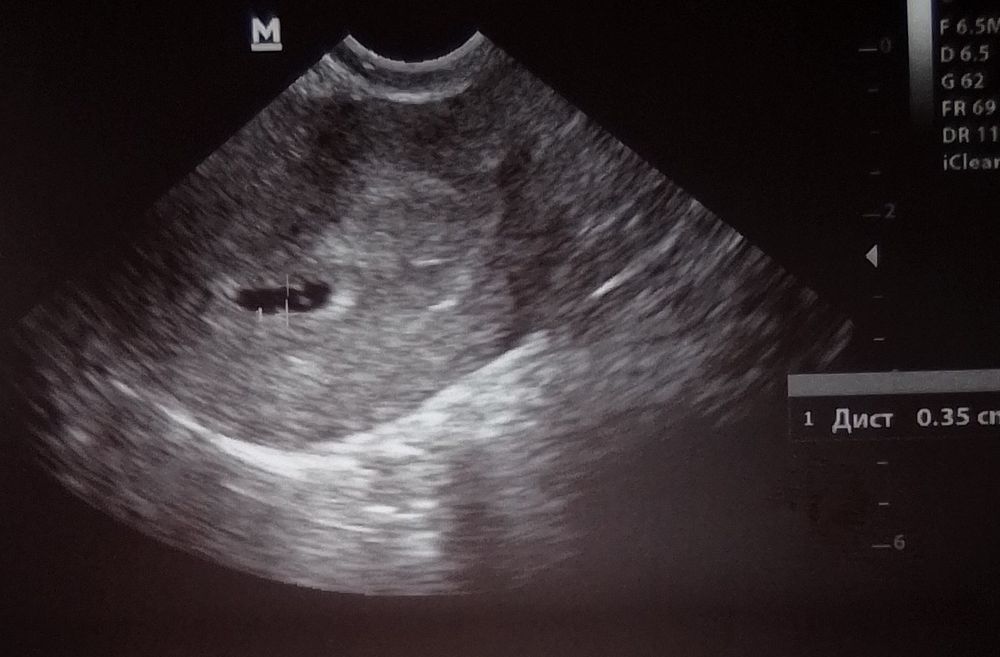

у меня больше недели коричневые выделения вчера была на узи сказали деформированное ПЯ

СРОК 5 недель 5 дней

Плодное яйцо D 27x5MM

желточный мешокчек 5.1ММ

Эмбриона не видно

говорят может зб